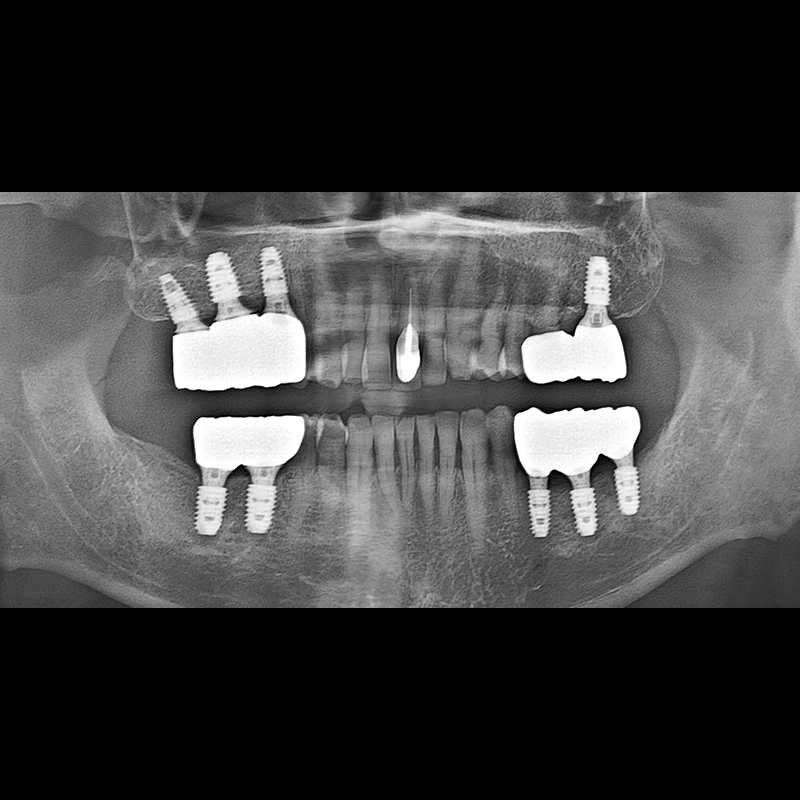

インプラント手術事例 2025.05.30

欠損した歯の部分と、生かしにくい歯の位置にインプラントを植立しました。